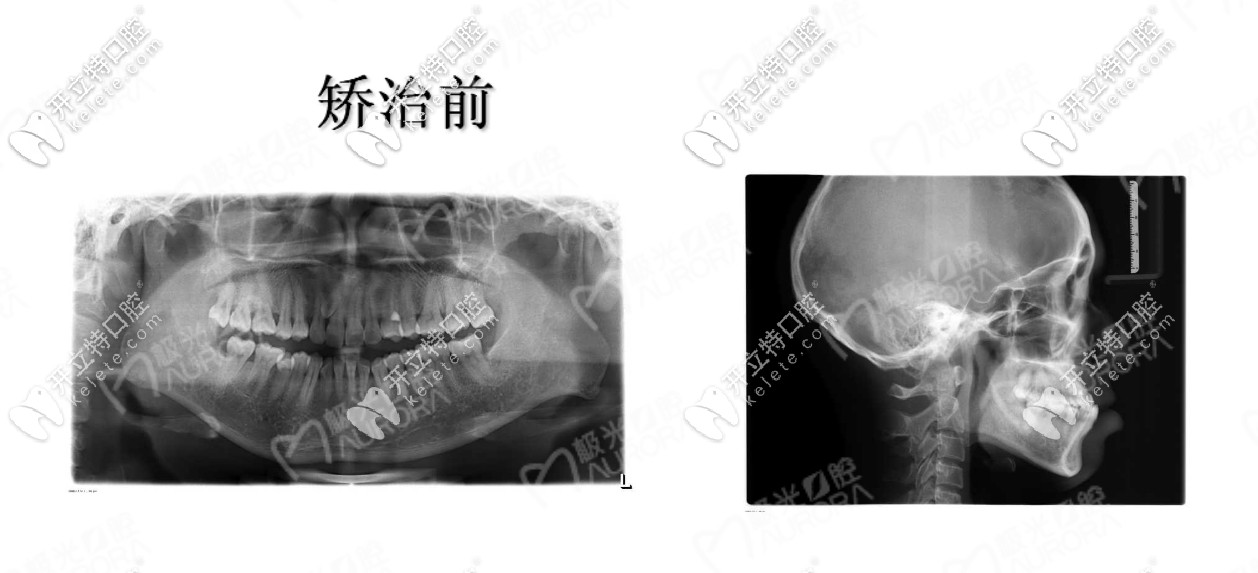

醫(yī)助結(jié)合我的需求給我介紹的醫(yī)生也很有耐心,拍片檢查后看我雖然是地包天,但是我的牙周情況良好,屬于牙性因素的反合。

門牙地包天怎么矯正

牙片真是個好東西,我終于全面看到了自己牙齒,說實話,有點嫌棄啊,醫(yī)生給我介紹的隱形矯正和鋼絲矯正,但是為了美觀和方便,我選擇的是隱適美隱形牙套,因為隱適美會對推磨牙后移的矯正速度減少,具體醫(yī)生咋說的,我給忘啦!嗚嗚!